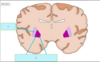

What type of brain herniations are A & B? [2]

A

A: Downward cerebellar (Tonsillar)

B: Upward cerebellar (transtentorial)

25

State what type of herniation A-D are [4]

A: **Cingulate** (Subfalcine) B: **Central** (**transtentorial**) C: **Uncal** D: Downward cerebellar (**Tonsillar**)